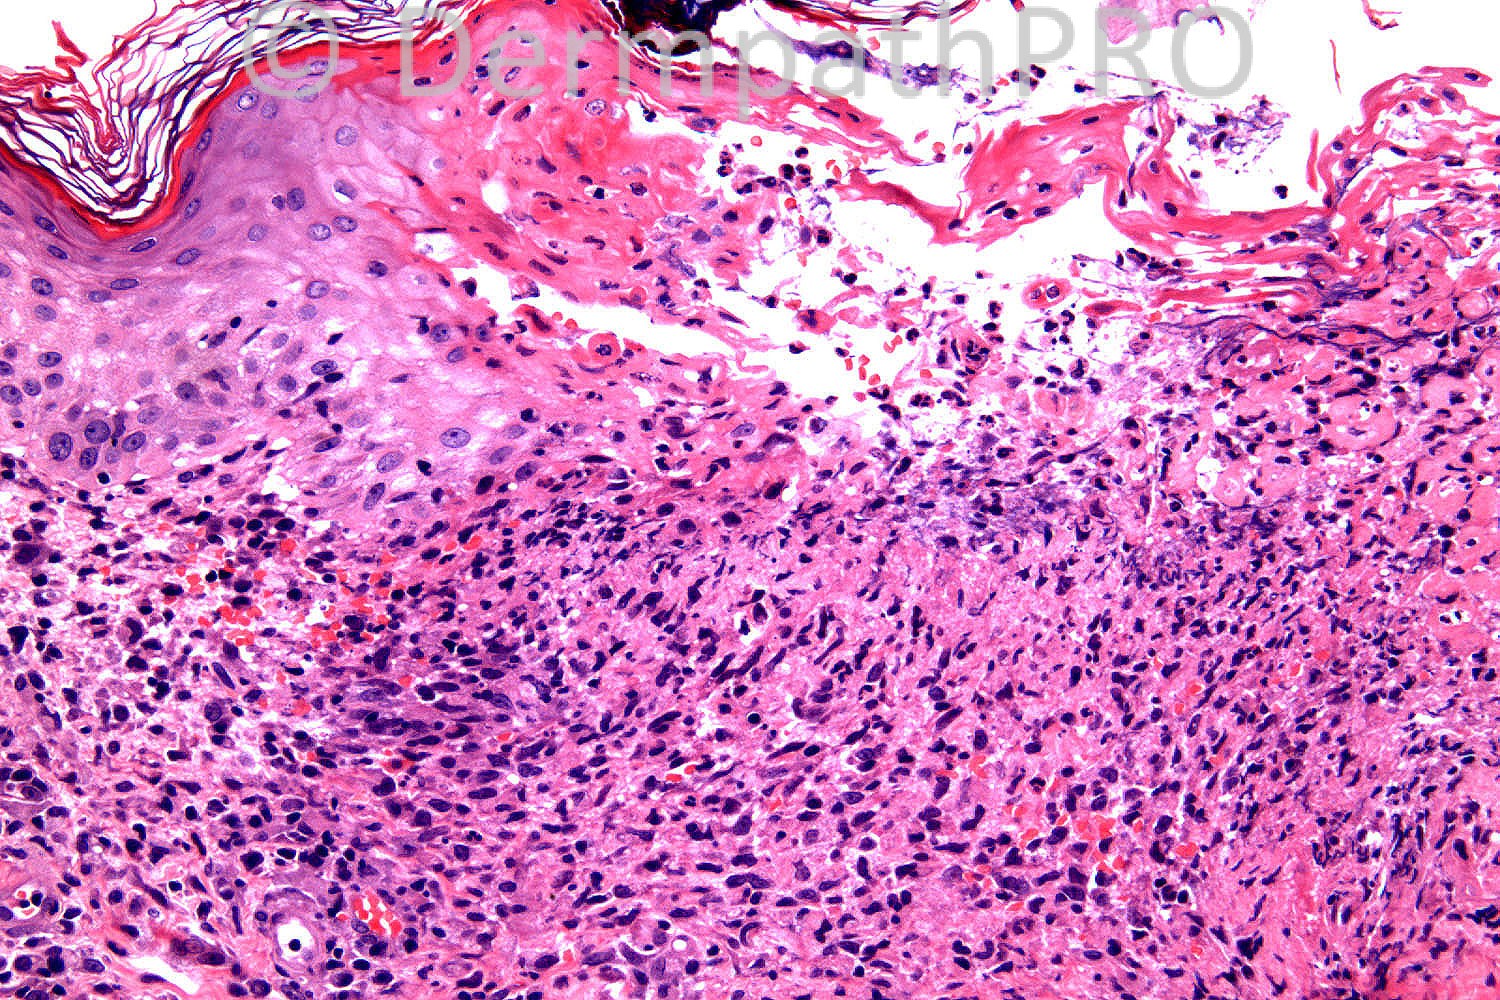

68 years-old female. 2 year history of itchy rash on buttock. Cropped pustules. ?DH.